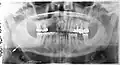

На панорамной рентгенограмме зубов видна зубная киста (отмечена стрелкой)